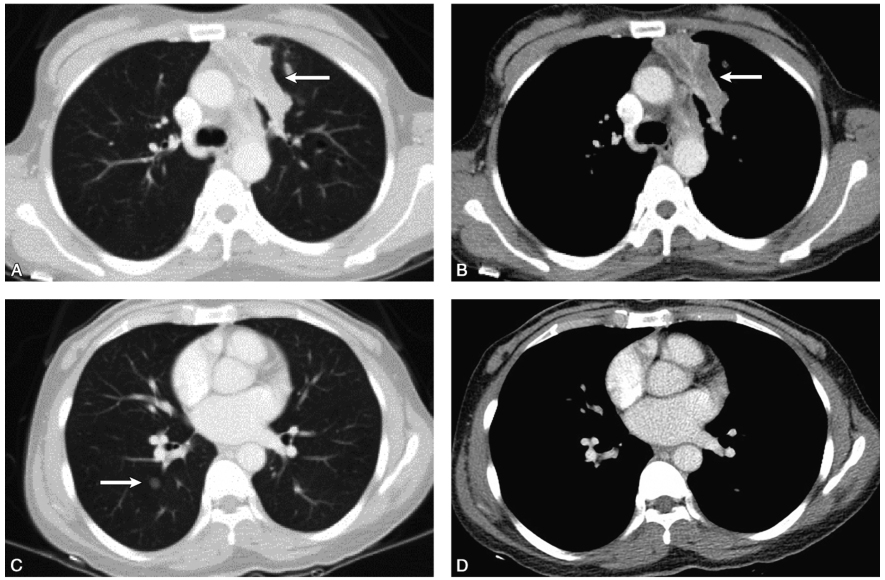

-胸部CT增强(2018-04-19):左肺上叶前段支扩伴感染,右肺下叶背段8mm磨玻璃结节(图1)。

图1胸部CT增强示左肺上叶前段支扩伴感染,右肺下叶背段8mm磨玻璃结节

A、B.白箭示支气管扩张,腔内见液性暗区;C.白箭示磨玻璃影;D.C图的纵隔窗表现